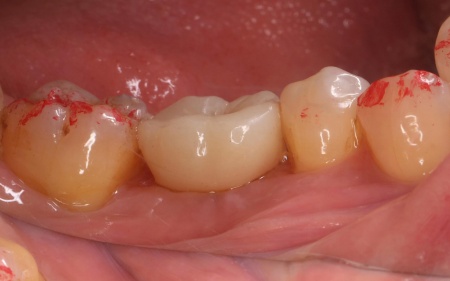

60代男性 歯が抜けている部位にインプラント治療を施した症例

拝見したところ、左下奥歯(第1大臼歯)が抜けており、見た目が気になるだけでなく奥歯でしっかりと噛むことが難しくなっていました。

②インプラントがあごの骨に問題なく定着したことを確認したあと、インプラントの上に人工歯を装着する

最後に見た目や噛み合わせに問題がないことを確認し、治療を終了しました。